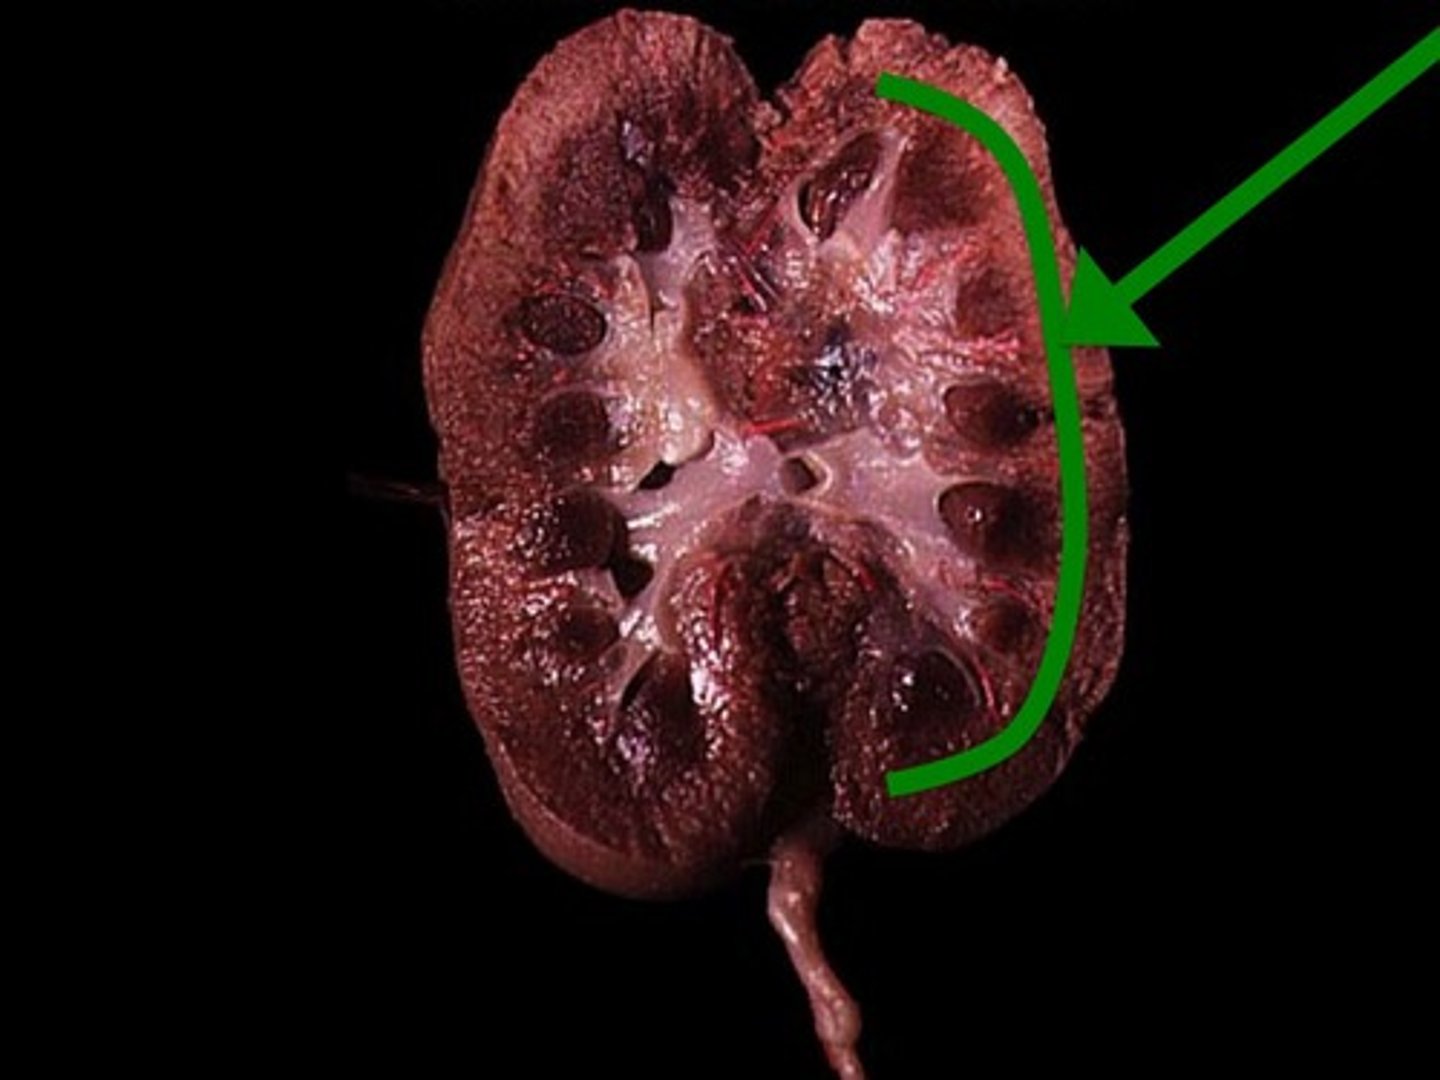

Renal Cortex

Renal Medulla

Renal Pyramid

Renal Column

Renal Pelvis

Ureter